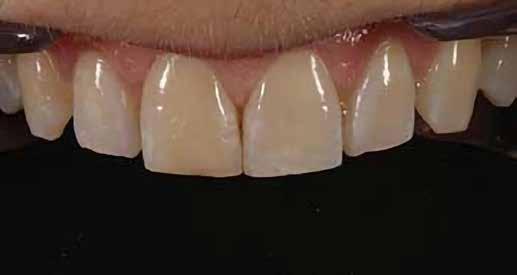

A fogászati kezelések során manapság már nem kizárólag az esztétikai megjelenés helyreállítására törekszünk. Sokszor a kedvezőtlen esztétikai megjelenés hátterében álló okok következményes módon a fogazat funkcionális működését is károsítják, így a kezelések során ezeknek a helyreállításával is foglalkoznunk kell. A különböző funkcionális és esztétikai diszkrepanciák kezelésére számtalan módszer létezik, ám ezen fogászati beavatkozások mindegyikében közös, hogy a kivitelezésük során nagyon szoros együttműködésre van szükség a kezelést végző fogorvos és a munkáját segítő fogtechnikus között. Az alábbi esetbemutatás során egy fiatal hölgypáciens fogazatának héjak alkalmazásával történő esztétikai és funkcionális rehabilitációját szeretnénk ismertetni.

A 19 éves hölgypáciens azzal a kéréssel jelentkezett a rendelőnkbe, hogy szebb fogakat szeretne. Az első konzultáció alkalmával megkérdeztük, hogy mi zavarja leginkább a fogazatának jelenlegi megjelenésében, valamint azt is megbeszéltük vele, hogy milyen végeredmény elérése esetén lenne maradéktalanul elégedett. Ebben az esetben a kezelési célokat az alábbiakban határoztuk meg:

A páciens fogazata esztétikai megjelenésének és funkcionális működésének a lehető legtöbb, saját foganyag megtartása mellett történő helyreállítása (1. és 3. ábra).

A kezelés megtervezése során kifejezett jelentősége van annak, hogy jó kommunikáció legyen a páciens, a fogorvos és a fogtechnikus között. A páciens leendő fogazatának természetes megjelenését a kezelésben részt vevő team szakmai felkészültsége, gyakorlati tapasztalata és a kezelés sikerességének irányába történő elkötelezettsége biztosítja. A beavatkozások megkezdése előtt megtörtént a páciens anamnézisének a felvétele, valamint a klinikai kivizsgálását is elvégeztük. Ezt követően lenyomatokat készítettünk a kiindulási állapotról, majd a kiindulási helyzetet extra- és intraorális fotók segítségével is rögzítettük (13. a-c. ábra).

A kezelés során az jelentette a legnagyobb kihívást, hogy a héjakkal ellátott fogak élethűen utánozzák a természetes fogazat megjelenését. A fogpótlás színének, valamint a restaurátumok felszíni textúrájának és alakjának harmonikusan kell a páciens arcesztétikájához és karakteréhez illeszkednie.

A tényleges protetikai ellátás megkezdése előtt a páciens mosolygás közben látható fogait otthoni fogfehérítés keretei között a kérésének megfelelő A1-es fogszín eléréséig fehérítettük. A fehérítés során a későbbiekben héjakkal ellátásra kerülő fogak színén nem változtattunk. A fogak előkészítése részeként csupán a két felső nagymetsző (1.1,2.1) incizális élét kellett kismértékben redukálni. A többi felső front fog (1.3,1.2,2.2,2.3) nem került preparálásra.